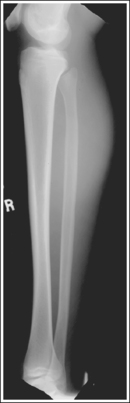

Image density is uniform across the lower leg.

The lower leg demonstrates an AP projection. The tibia demonstrates only minimal superimposition of the proximal and distal fibula, and the fibular midshaft is demonstrated free of tibial superimposition.

• Detecting lower leg rotation. Rotation of the lower leg can be identified on an AP lower leg projection by evaluating the relationship of the fibula to the tibia. When the patient's leg is externally (laterally) rotated, the fibula shifts toward and eventually beneath the tibia, obscuring the medial mortise (see Image 48). When the patient's leg is internally (medially) rotated, the head of the fibula draws from beneath the tibia (see Image 49).

The tibial midshaft is at the center of the exposure field. The tibia, fibula, ankle, knee, and surrounding lower leg soft tissue are included within the collimated field.